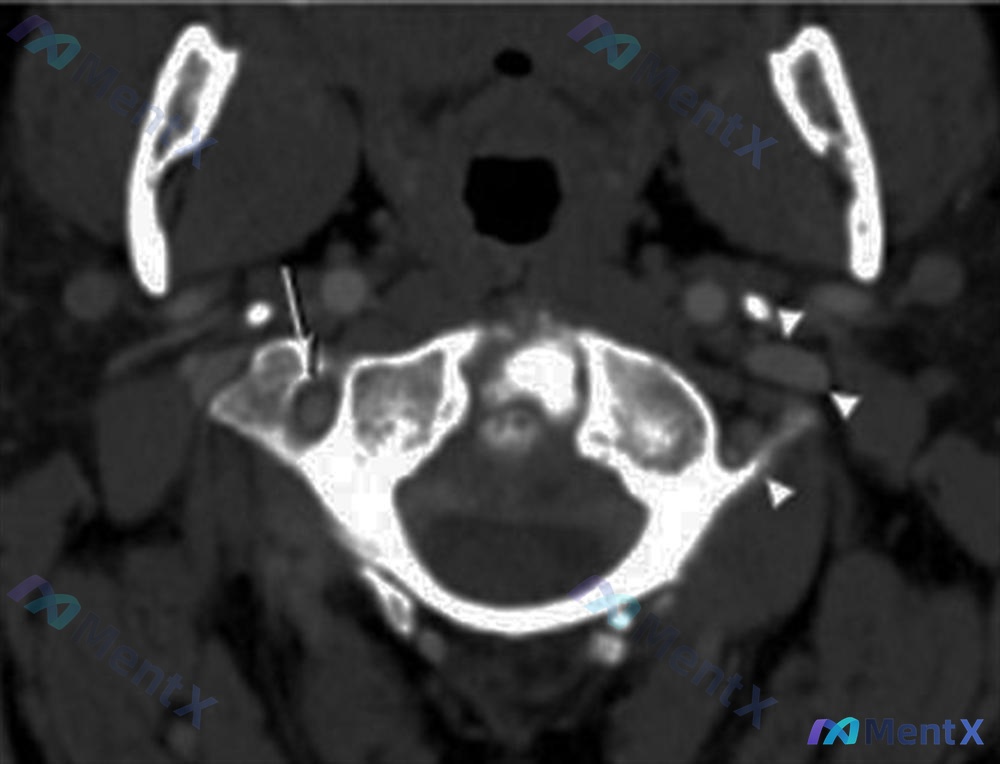

- 影像:张口颈椎X光片、矢状位CT、CT轴位血管造影

影像分析提示:

- 枢椎(C2)齿状突基底部骨折,骨折块与椎体分离

- 齿状突骨折块伴随寰椎向前移位,寰枢关节不稳/半脱位

- 寰枢复合体稳定性完全丧失,需警惕脊髓/延髓压迫风险